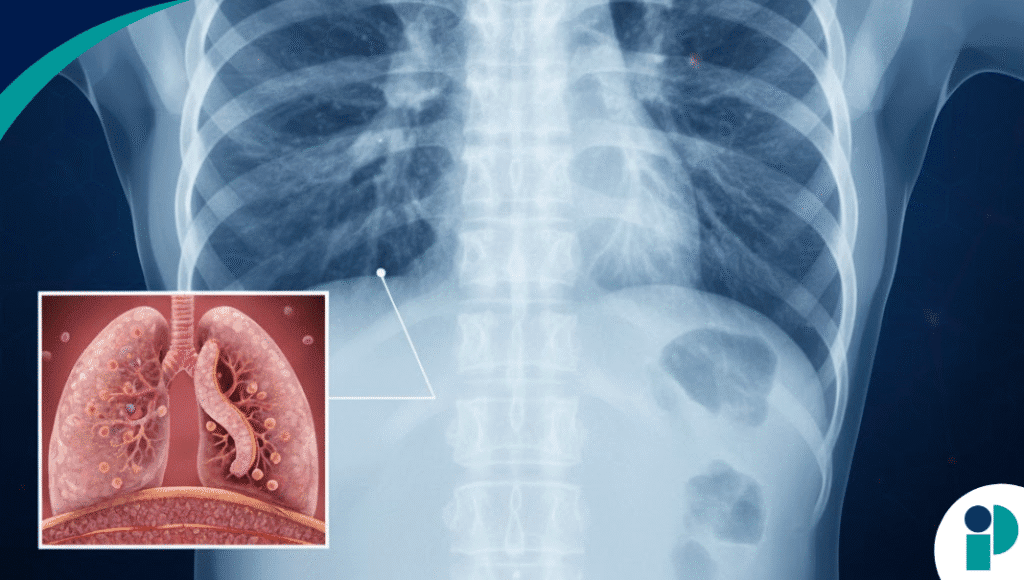

Los estudios de imagen suelen mostrar opacidades en vidrio esmerilado y consolidaciones bilaterales, mientras que los análisis de laboratorio pueden revelar leucocitosis, elevación de PCR y alteraciones hepáticas leves.

- Infiltrados bilaterales en radiografía o tomografía.